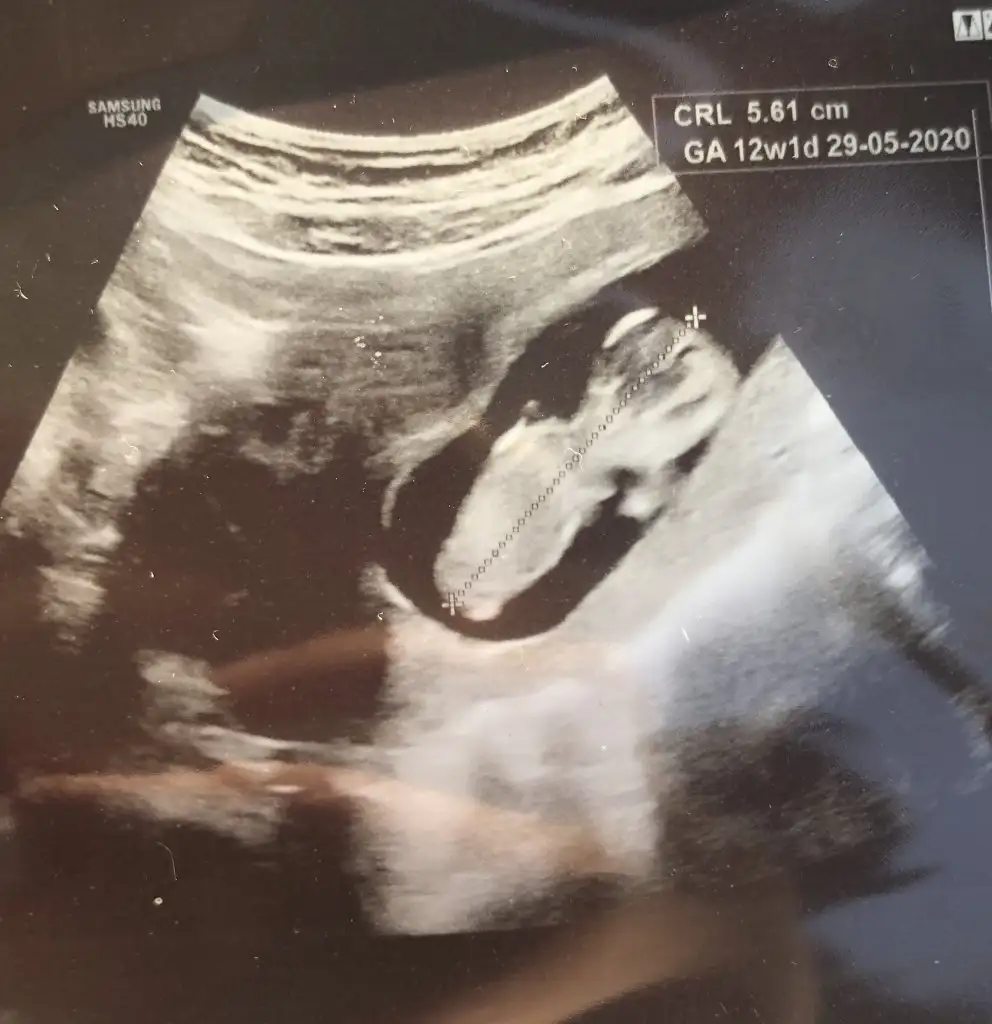

dr soylemeden siz gorun genital nub teorisi ( bebegin cinsiyeti)

Kızlar yorum istiyorum doktor daha küçük dedi 12 haftada ☺️☺️